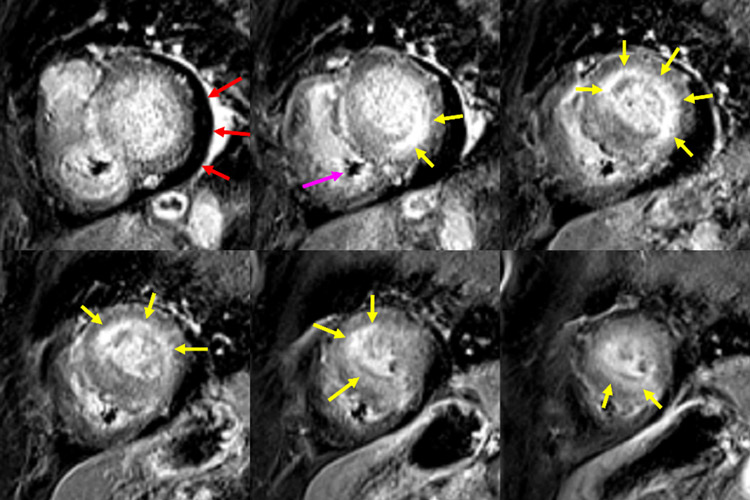

Figure 2 : Cartographie T1 pré et post injection de gadolinium

Coupes petit-axe basal, médian et apical

La mesure de l’hématocrite permet de calculer la formule du volume extracellulaire (ECV) mesuré à 41 %.

Figure 6 : Cartographie T1 pré et post injection de gadolinium - Coupes petit-axe basal, médian et apical

Valeur d’ECV mesurée à 41 %.

- La mesure du T1 mapping à 1 070 ms n’est pas très élevée pour l’âge du patient (norme < 1 100 ms pour cet âge).

- Par contre, la mesure du volume extracellulaire (ECV) est franchement élevée à 41 % (norme < 27 %).

- À noter que cette divergence entre T1 mapping normal et ECV élevé peut notamment être décrite chez les patients avec amylose cardiaque.

Figure 7 : Séquence de perfusion premier-passage au repos

Présence d’une hypoperfusion sous-endocardique diffuse (flèches jaunes) correspondant à des troubles de la microcirculation décrits sur les modèles animaux d’amyloses cardiaques.